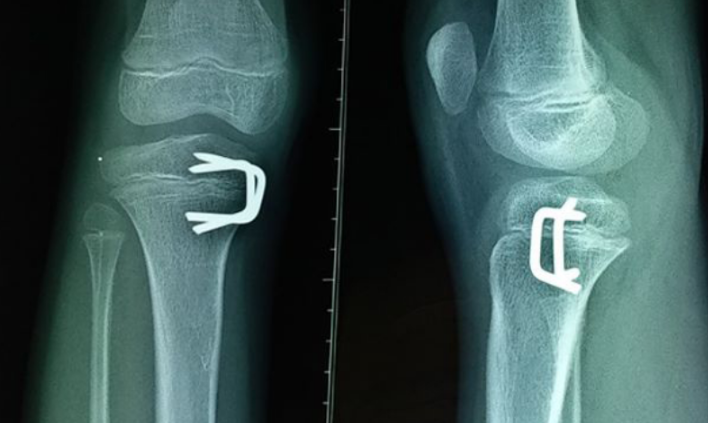

Phương pháp điều trị gãy sụn tăng trưởng là thường dùng nẹp hoặc bó bột. Đôi khi, phải xếp xương trở lại vị trí để xương lành lại ở vị trí chính xác. Việc xếp xương có thể được thực hiện trước hoặc sau khi bó bột. Thời gian bó bột hoặc bó nẹp khác nhau tùy thuộc vào vị trí và mức độ nghiêm trọng của vết gãy sụn. Trẻ em thường mau lành hơn người lớn tuổi.

Phẫu thuật được chỉ định cho một số trường hợp gãy sụn tăng trưởng, đảm bảo sụn tăng trưởng được căn chỉnh tối ưu để xương đó phát triển bình thường. Phẫu thuật là bộc lộ xương và cố định bằng vít và đĩa để giảm mở và cố định bên trong.